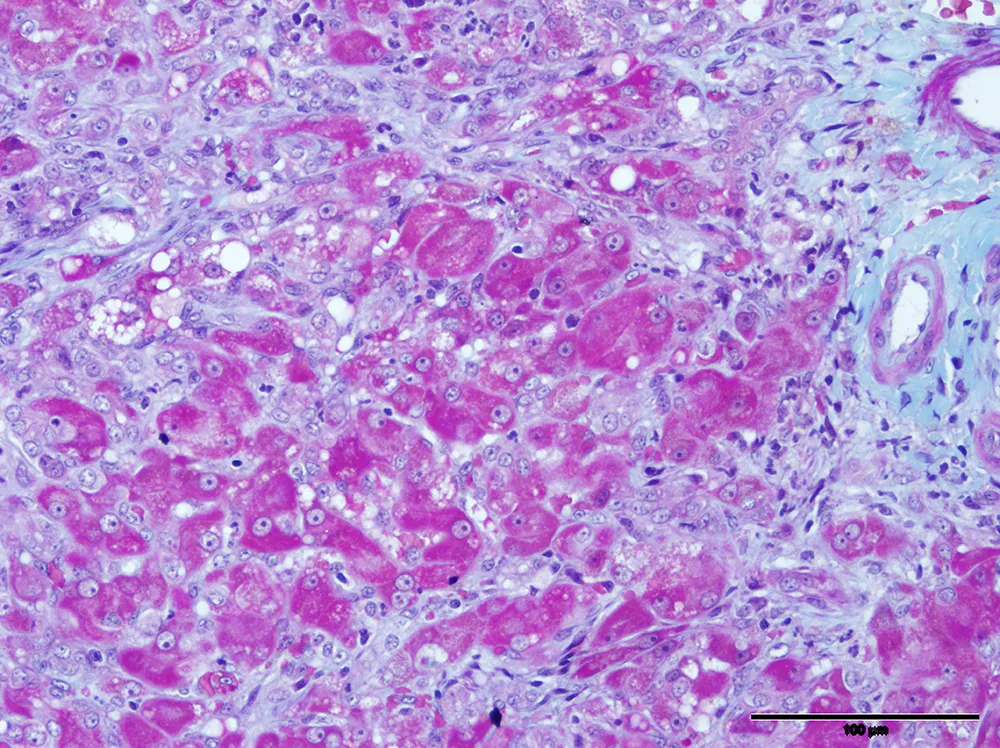

Presence of Systemic Inflammatory Response Syndrome Predicts a Poor Clinical Outcome in Dogs with a Primary Hepatitis

This allows internal organ damage to be detected early in the disease process and without the need for an invasive biopsy. One example of this work is our discovery that miR-122 is an accurate test for the detection of liver disease in dogs